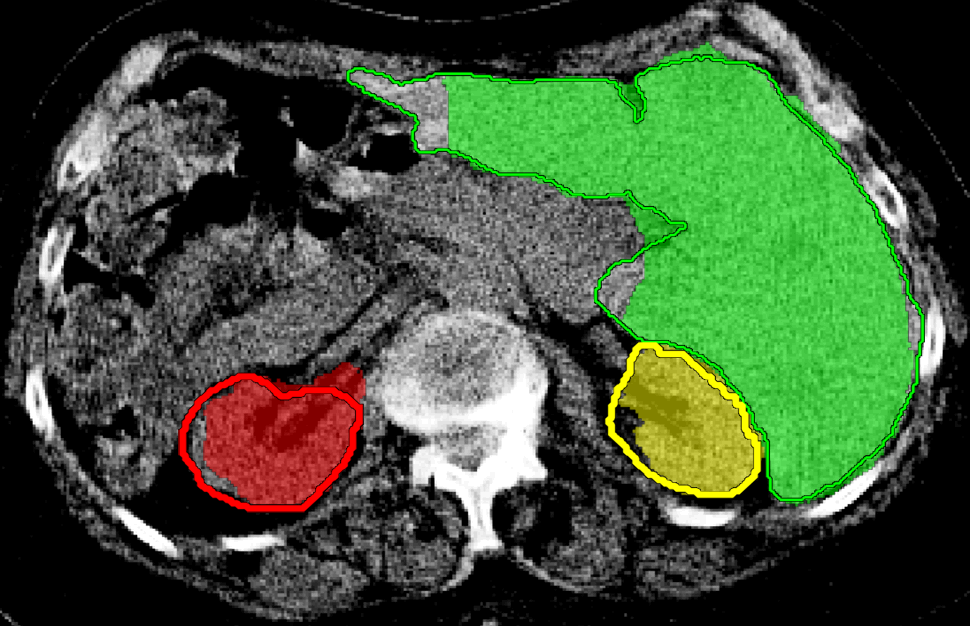

We applied our method on PET-CT scans of three different subjects to segment their liver, left kidney, right kidney and the background. Although we applied our method and Potts model on the 3D volumes we only show the results on a few representative slices from each volume in Fig.11. Also, the results of different methods for each subject were computed using the same smoothness. We can see from the last two rows which compare our method to Potts, using Hedgehogs constraints enabled us to avoid geometrically incorrect segmentations, e.g. one liver inside the other (last-row middle), or parts of left kidney is between the right kidney and liver (last-row right). Furthermore, for test subjects 1 and 2 the kidneys and background were poorly segmented by Potts model, e.g. most of the kidneys were segmented as background for test subject 1. Potts poor performance is due to the large overlap between the kidneys and background color models. This overlap resulted in an in-discriminative data term for Potts to properly separate them. This issue becomes worse in iterative frameworks where color models are re-estimated based on current segmentation. To be specific, if at any iteration Potts model resulted in a bad segmentation then re-estimating the color models will bias them towards the bad segmentation and subsequent iterations worsen the results. Comparing our results for subjects 1 and 2 to Potts model shows that our method is less prone to the aforementioned issue as we forbid undesirable segmentations, i.e. those that do not respect shape constraints.

| Subject 1 | Subject 2 | Subject 3 | |||

| Our method (Hedgehogs Shapes + Potts) | ![]() |

![]() |

||

|||

| \rdelim}1910pt Same Slice | |||||

|

Potts |

For quantitative comparison, Table 1 lists for each organ of a subject the Score, Precession and Recall measures of our method and Potts model where For the kidneys, our method clearly out performed Potts model, e.g. note Potts model poor precision/recall for subjects 1 and 2. For the liver, both methods performed comparably.